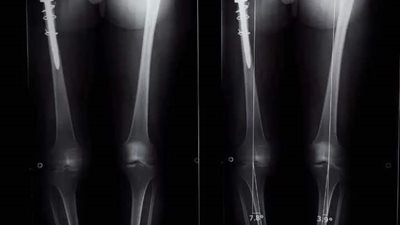

نجح فريق طبي من قسم جراحة العظام بمستشفى أسيوط الجامعي، في إجراء أول جراحة من نوعها؛ لاستئصال ورم من عظمة الآلية،